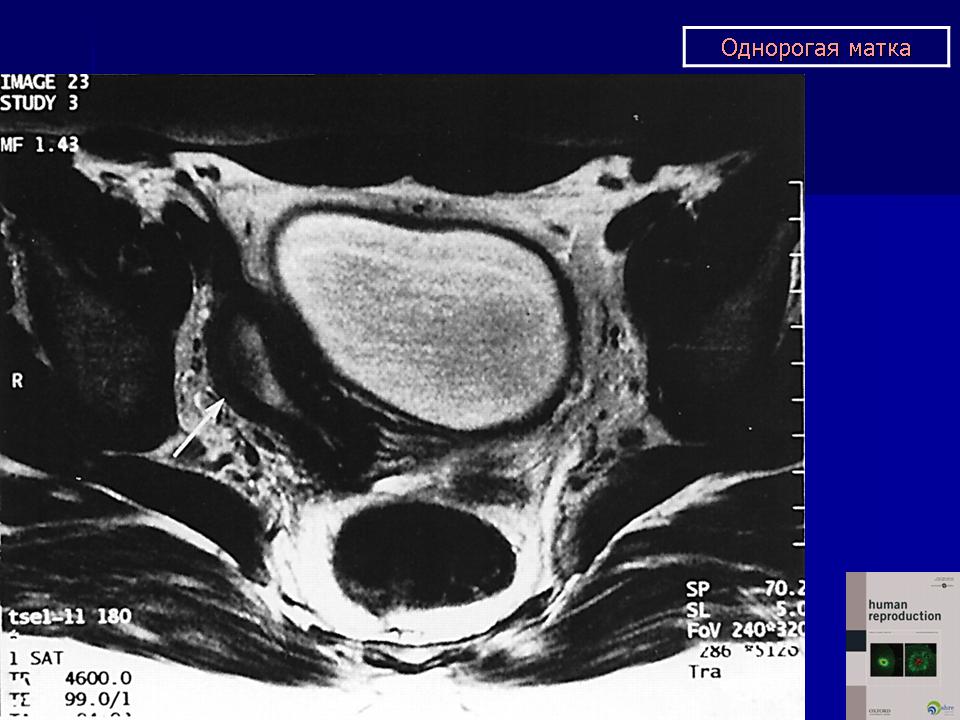

МПС. Женская репродуктивная система. Аномалии и варианты развития. Матка. Однорогая матка. +

Аномалии и варианты развития. Однорогая матка.